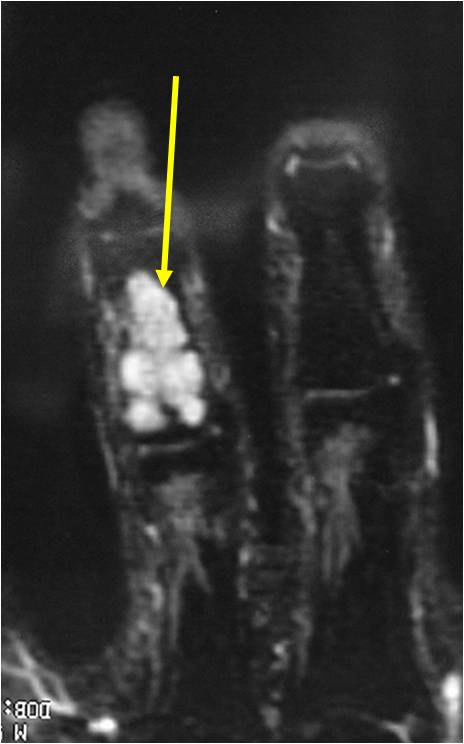

MRI:

- Lobulated margin (Lobular Growth Pattern)

- T2 Weighted Images: High Signal Intensity

- High water content shows as high signal on T2 weighted images

- Calcifications will be low signal

T2: High Signal No Soft Tissue Component